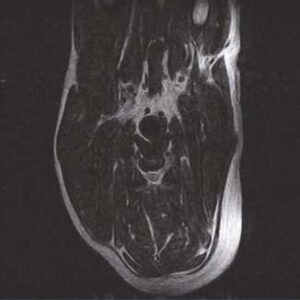

The PANION PRO comes with the double-pole open magnet design with a wide opening gap of 40 cm to accommodate large-sized animals on an efficient patient handling platform, the strongest gradient amplitude at 33mT/m and slew rate of 90 T/m/s, among all other open MRI systems, resulting in high spatial resolution of images in short scan time. The 6-direction patient table permits iso-centre imaging of all anatomical regions.

Clinical Images